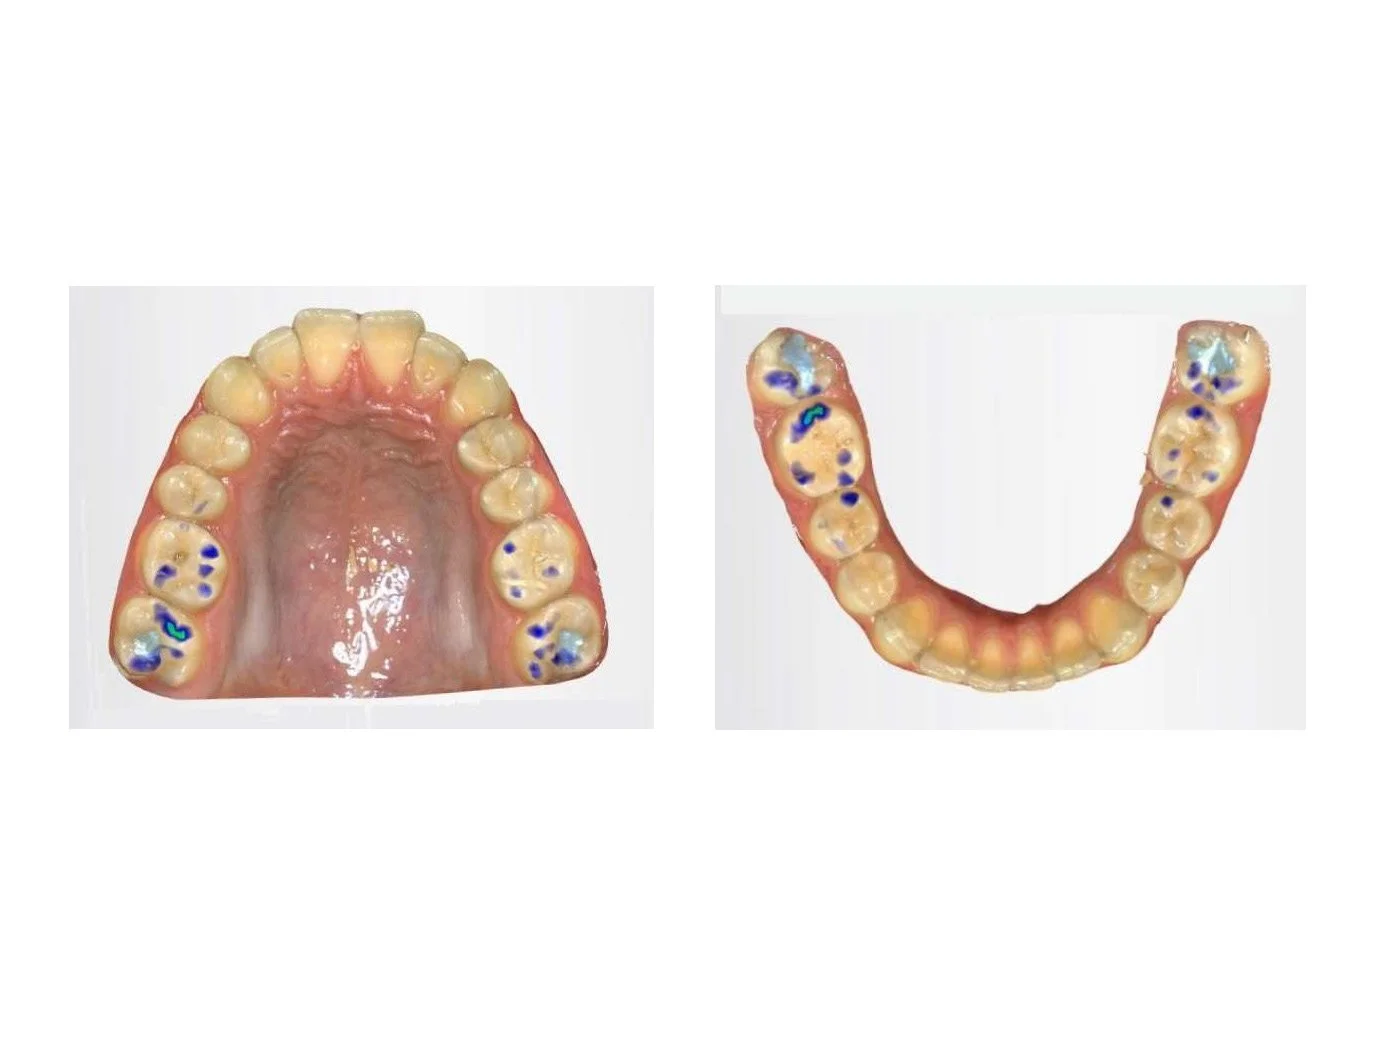

À l’examen intra-oral, on observe un surplomb horizontal de 6,0mm en IM et de 7,0mm en AC. Ceci se traduit évidemment par une classe II au niveau dentaire également en postérieur. Aussi, le patient présente une béance antérieure jumelée à une position antérieure de la langue au repos ainsi qu’à la déglutition. Ceci est sans surprise vu la nécessité de sceller la béance pour bien avaler. Finalement, la position linguale antérieure, a également, de façon typique, conduit à un déficit de la dimension transverse du maxillaire tel qu’on peut l’observer sur les photos intra-orales. Ceci démontre bien l’importance de déceler en bas âge les dysfonctions musculaires orales afin de pouvoir les traiter et ainsi d’en limiter les conséquences néfastes sur la croissance oro-faciale future.

En AC, seules les dents 17 et 46 sont en contact tel que le montrent les captures d’écran d’un modèle 3D. Cette instabilité occlusale force le patient à glisser d’environ 1,0mm antérieurement et 0,8mm vers la gauche, de sorte à rétablir des contacts du côté gauche aussi. Ce glissement ainsi que cette répartition inégale des forces masticatoires ont le potentiel de causer plusieurs problèmes :

Le plan de traitement idéal consiste en l’exécution d’une expansion palatine rapide dans les plus brefs délais, puisqu’on estime que notre patient est déjà passé la moitié de son pic de croissance. Afin de réduire les forces au niveau des articulations temporo-mandibulaires un appareil d’expansion constitué d’un recouvrement occlusal en acrylique a été utilisé et ajusté méticuleusement à quelques reprises en cours d’expansion.

Évidemment, étant donnée l’instabilité de l’occlusion d’ici là, il a été fortement recommandé au patient de porter une plaque occlusale la nuit entre les deux phases de traitement orthodontique. Ceci aura l’avantage de permettre de mieux répartir les forces occlusales sur les dents au moment où les parafonctions sont plus difficiles à contrôler, ainsi que de réduire ainsi la charge articulaire.